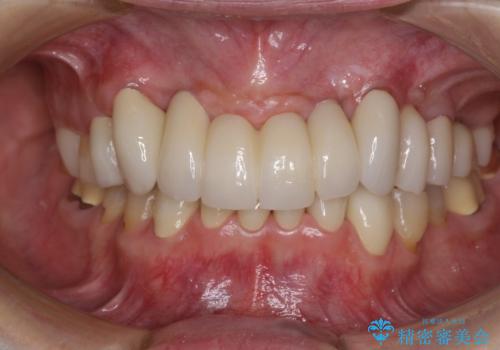

銀歯や入れ歯で汚い歯をきれいにしたい 総合歯科治療

歯並びや奥歯の痛み 色々と治したい 総合歯科診療

歯列不正と歯周病 総合歯科治療による全顎治療

気になる部分を全て治療 総合歯科治療で口腔内環境改善

歯周病改善のための総合歯科治療